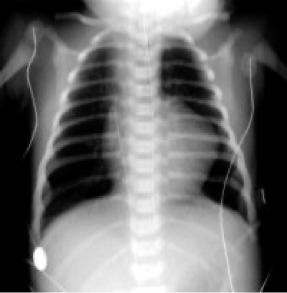

Pulmonary Atresia